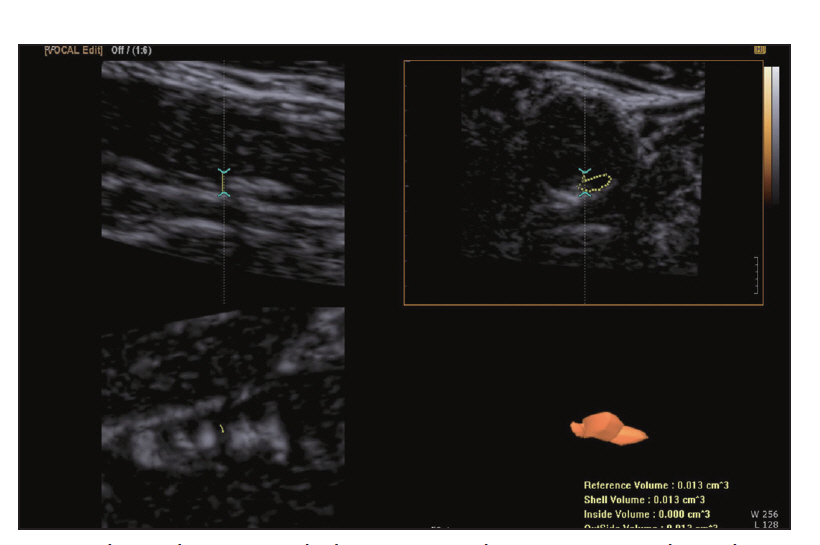

Carotid Doppler ultrasonography is a popular tool for evaluating atherosclerosis of the carotid artery. Its two-dimensional gray scale can be used for measuring the intima-media thickness, which is very good biomarker for atherosclerosis and can aid in plaque characterization. The plaque morphology is related to the risk of stroke. The ulceration of plaque is also known as one of the strong predictors of future embolic event risk. Color Doppler ultrasonography and pulse Doppler ultrasonography have been used for detecting carotid artery stenosis. Doppler ultrasonography has unique physical properties. The operator should be familiar with the physics and other parameters of Doppler ultrasonography to perform optimal Doppler ultrasonography studies.